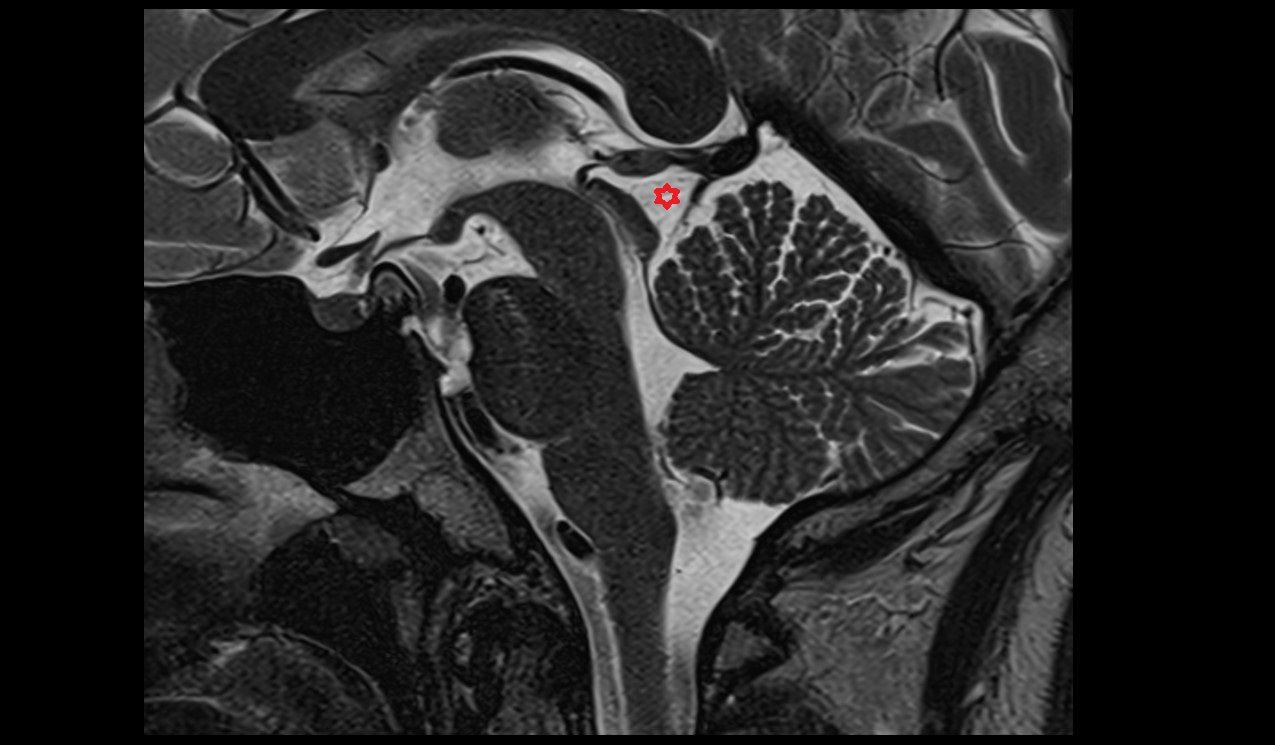

- Cerebral aqueduct

- Superior opening of cerebral aqueduct

- Aqueduct of midbrain (Sylvian Aqueduct)

- Fourth ventricle

- Median aperture of fourth ventricle (foramen of Magendie)

- Prepontine cistern

- Pontocerebellar cistern